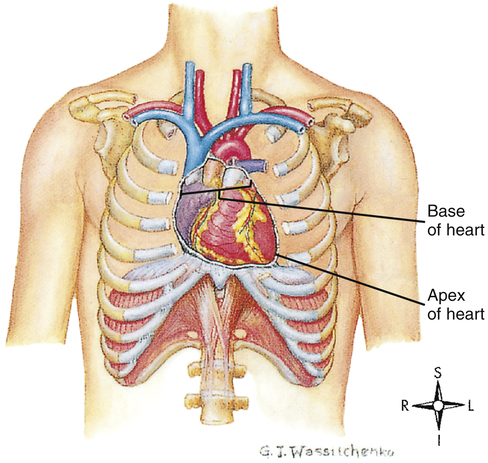

Анатомия Сердца: Расположение и Функции